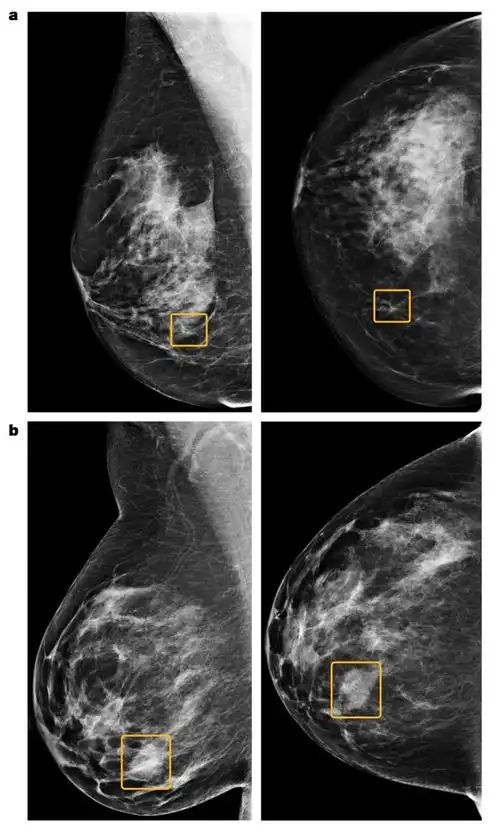

乳腺癌x线检查什么意思(钼靶x线检查)-帝国cms模板网